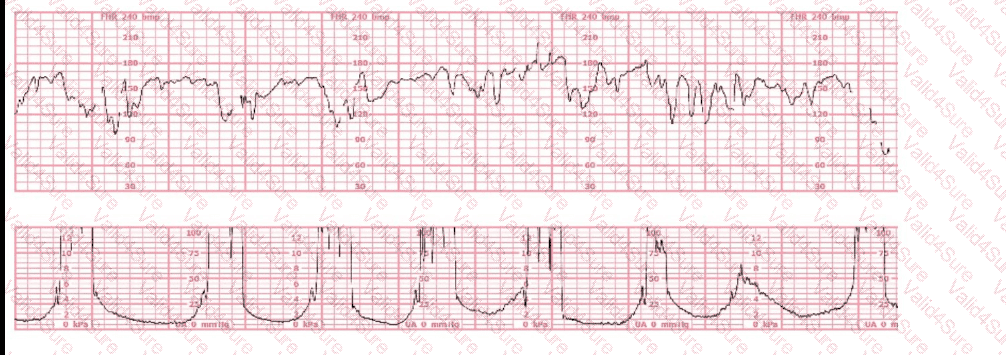

This fetal heart rate tracing is from a woman in the second stage of labor. This tracing is best interpreted as:

The most probable underlying fetal physiologic cause for this tracing would be: